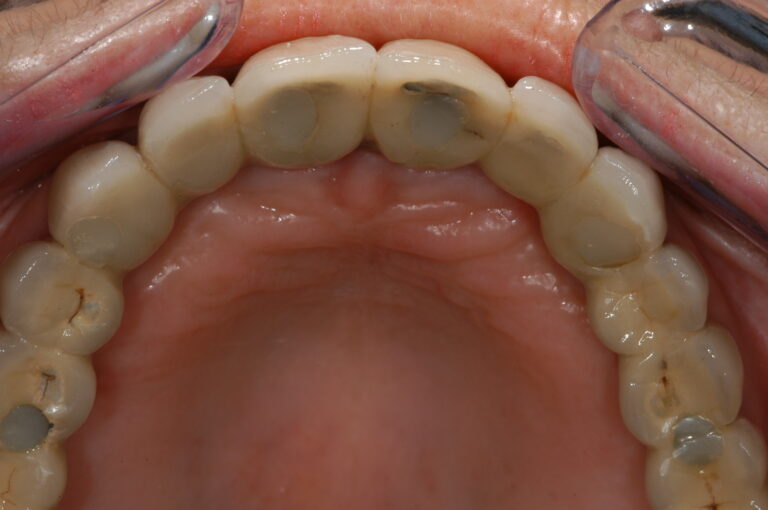

Following improvements to the surfaces of our implants, and utilising experience gained over many years, we can now offer you “FIXED TEETH TODAY”. In most cases, we are able to place a fixed bridge onto the implants immediately after placement. You would therefore arrive at the surgery with loose dentures, and leave with a number of implants placed and a FIXED bridge fitted onto them. This concept reduces the discomfort and healing time following implant placement, and provides immediate satisfaction to our patients. Imagine being able to bite into an apple again for the first time in many years!

The most common cause of partial tooth loss is failing crowns or bridges. The natural roots are then too weak to support a bridge, and have to be extracted. We would usually extract the failing roots, place implants directly into their sockets, and place a fixed bridge immediately afterwards.